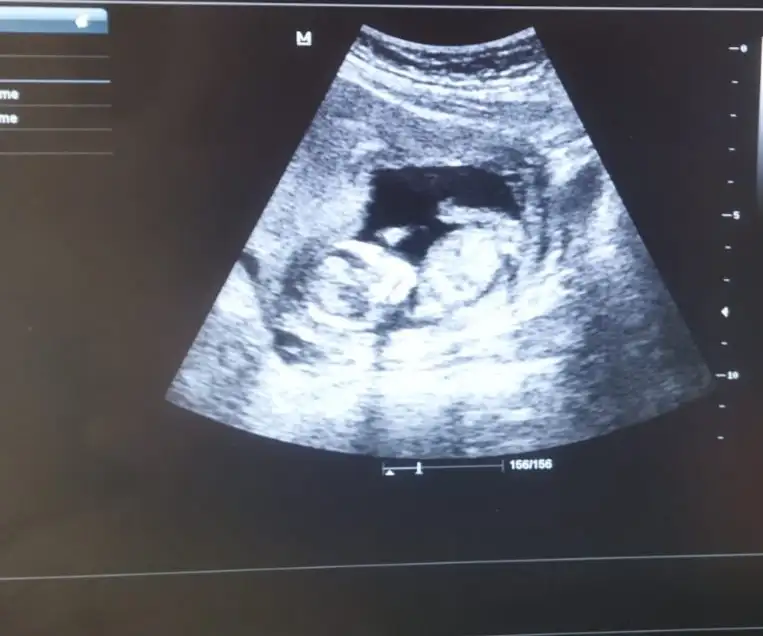

Canını sıkma hiç geç döllenme olmuştur sonradan yakalar haftasınıKızlar Selam gördük keseyi çok şükür bebek yok henüz. 6+1 olması gerekirken kesem 5 haftalık çıktı. Dr normal toparlar dedi ama benim canım çok sıkkın normal mi sizce yaşayan oldu mu böyle birseyPapatyamaviss 7.7 cm kese

Doktoruna guven kuzum olabılırKızlar Selam gördük keseyi çok şükür bebek yok henüz. 6+1 olması gerekirken kesem 5 haftalık çıktı. Dr normal toparlar dedi ama benim canım çok sıkkın normal mi sizce yaşayan oldu mu böyle birseyPapatyamaviss 7.7 cm kese